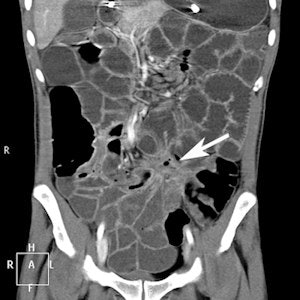

CTE coronal image of a patient with Crohn's disease. Value of CTE due to volume challenge is illustrated with fibrostenosing disease with fistulation. This can easily be missed on a nonvolume-challenged study.Based on the indications for referral, the largest group was the malabsorption/chronic diarrhea group with 19 (26.03%) referrals, according to van der Merwe and colleagues. In this group, one patient had celiac disease, one had Crohn's disease, and one had ulcerative colitis with terminal ileum involvement. The anemia group was the second largest with 13 (17.81%) referrals. In this group, no intestinal cause was identified for anemia. One patient had multiple uterine fibroids.